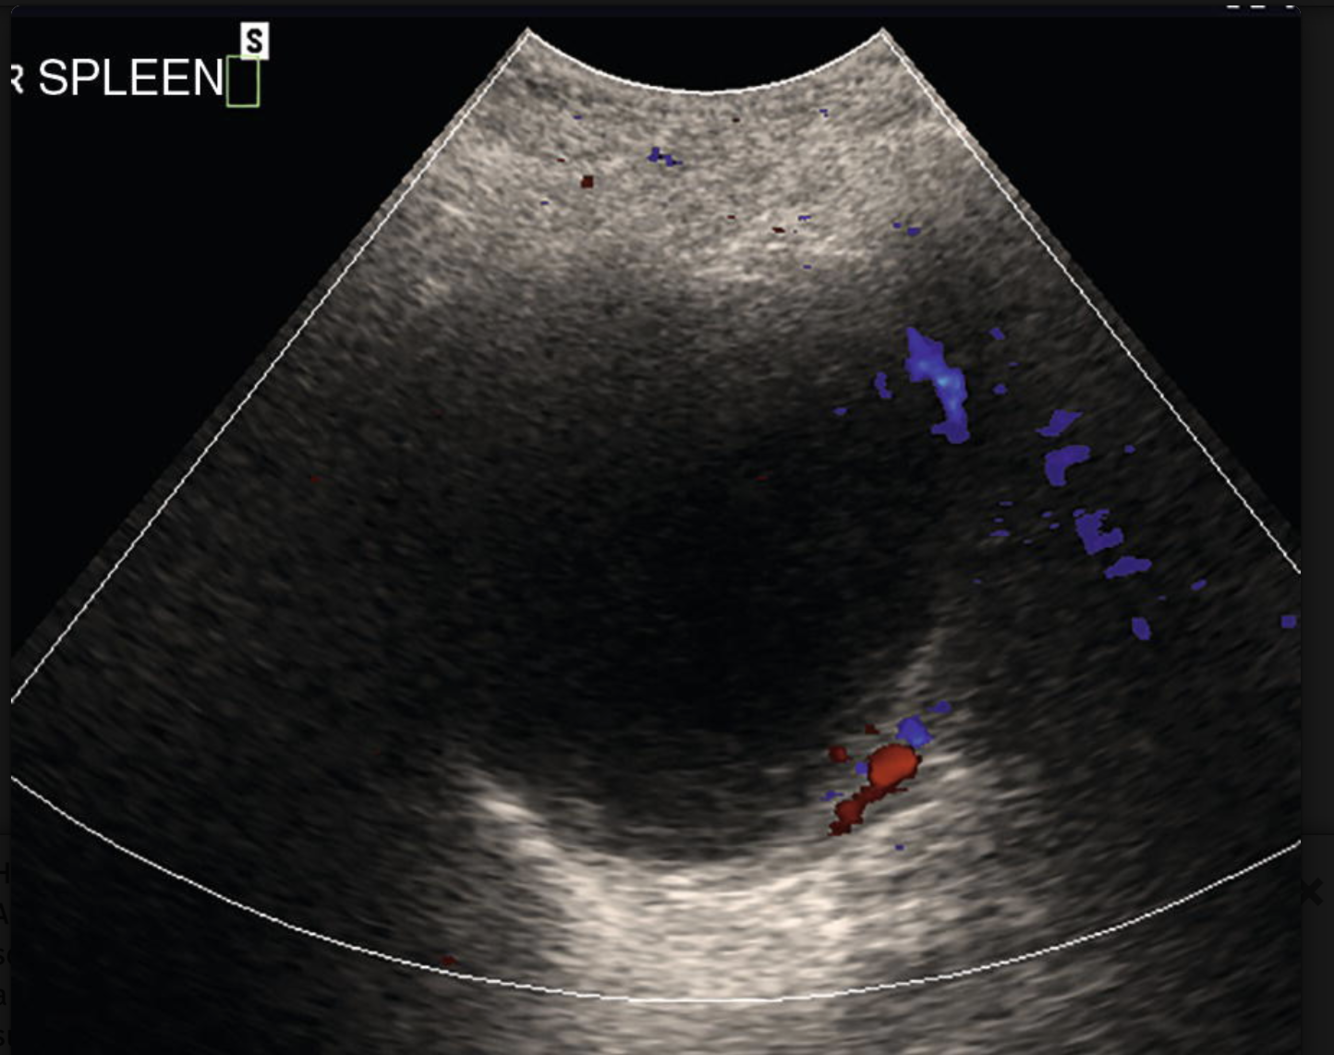

Name the most common benign splenic tumour.

Hemangioma.

These splenic findings are most commonly associated w/what process?

Gamna-Gandy bodies = PHTN.